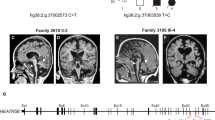

The ciliopathy Joubert syndrome is marked by cerebellar vermis hypoplasia, a phenotype for which the pathogenic mechanism is unclear1,2,3. To investigate Joubert syndrome pathogenesis, we have examined mice with mutated Ahi1, the first identified Joubert syndrome–associated gene4,5. These mice show cerebellar hypoplasia with a vermis-midline fusion defect early in development. This defect is concomitant with expansion of the roof plate and is also evident in a mouse mutant for another Joubert syndrome–associated gene, Cep2906,7. Furthermore, fetal magnetic resonance imaging (MRI) of human subjects with Joubert syndrome reveals a similar midline cleft, suggesting parallel pathogenic mechanisms. Previous evidence has suggested a role for Jouberin (Jbn), the protein encoded by Ahi1, in canonical Wnt signaling8. Consistent with this, we found decreased Wnt reporter activity at the site of hemisphere fusion in the developing cerebellum of Ahi1-mutant mice. This decrease was accompanied by reduced proliferation at the site of fusion. Finally, treatment with lithium, a Wnt pathway agonist9, partially rescued this phenotype. Our findings implicate a defect in Wnt signaling in the cerebellar midline phenotype seen in Joubert syndrome that can be overcome with Wnt stimulation.

J.G.G. and M.A.L. conceived of and designed the experimental approach, interpreted data and wrote the manuscript. M.A.L. and D.J.G. carried out in vivo characterization experiments. M.A.L. performed in vitro Wnt assays. J.K. and Y.W. designed and generated Cep290-mutant mice. S.N.S. and M.S.Z. performed human diagnoses and provided MRIs. J.L.S. generated constructs and materials for in vitro assays. C.M.L. and B.E.T. contributed to in vivo characterizations. J.G.G. directed and supervised the project.